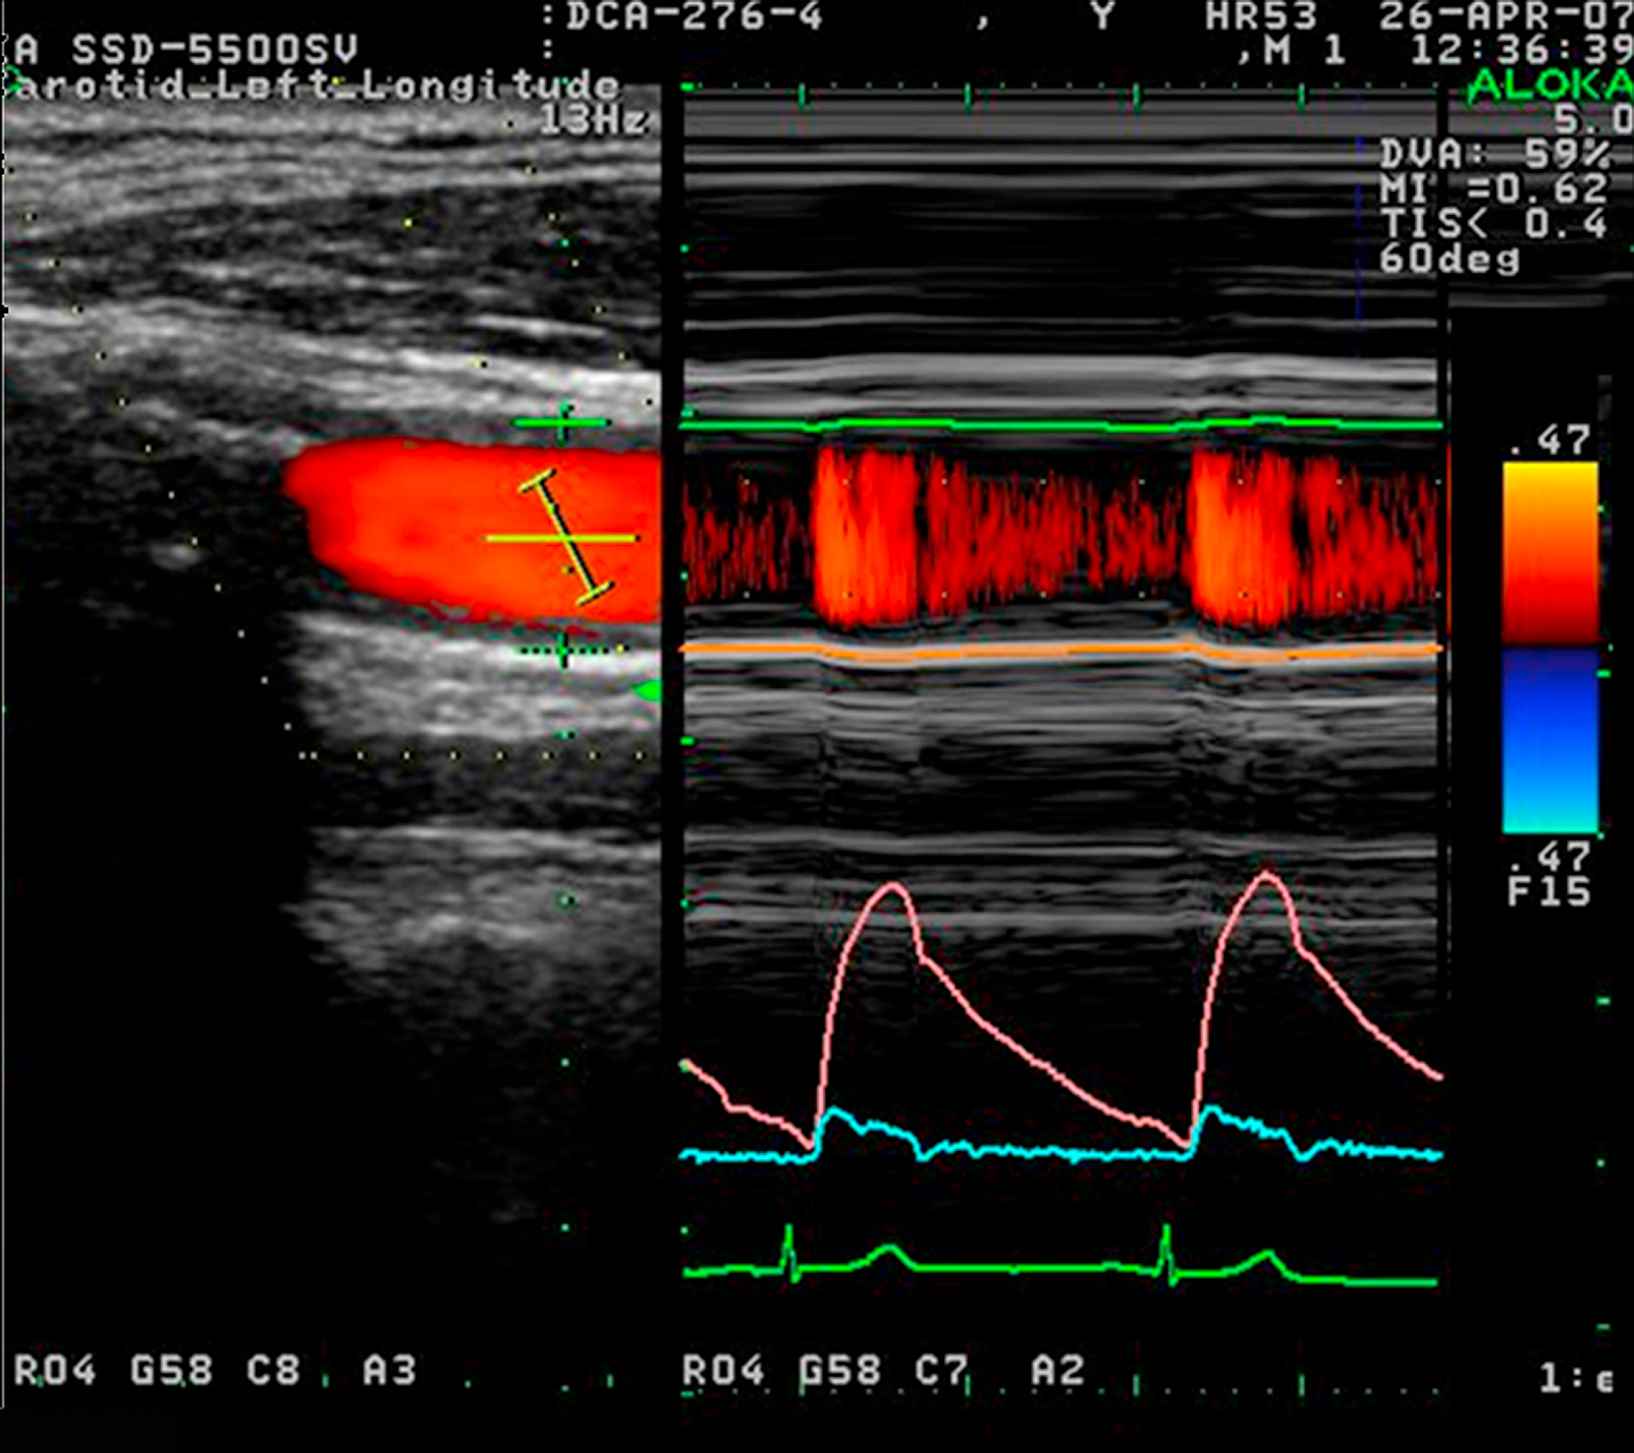

Non-invasive wave intensity analysis in the carotid artery measured using ultrasound. Flow velocity was calculated from colour Doppler (lower right panel, blue) while the change in arterial diameter was measured using a wall tracking method (middle right panel, pink) and calibrated to pressure using a brachial sphygmomanometry. All measurements were made using an Aloka SSD-5500 and commercial software.